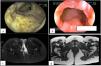

A 34-year-old woman had an 8-year history of CD. She initially presented with a moderate bout of the disease, with ileocolonic involvement and anal fissures (Fig. 1a and b). Induction therapy was infliximab 5 mg/kg IV at weeks 0, 2, and 6, followed by 5 mg/kg IV infusion every 8 weeks as maintenance therapy. The patient was in clinical and endoscopic remission for one year, after which she presented with numerous bouts of mild disease, characterized by deep anal fissures that remitted with prednisone 1 mg/kg/d VO, but became corticoid dependent. She then presented with a left-sided perianal abscess and 2 complex perianal fistulas that were treated with ciprofloxacin 500 mg every 12 h and metronidazole 500 mg every 8 h for 3 months, along with setons for 8 months, curing said complications (Fig. 1c and d). The patient continued to present with several mild bouts of anal fissures that improved with prednisone 1 mg/kg/d, but they were corticoid dependent. Infliximab dose was increased to 10 mg/kg IV every 4 weeks, combined with azathioprine 2 mg/kg/d. At one year there was no clinical improvement, and so anti-infliximab antibodies and serum infliximab levels were measured (0.1 AU/mL and 17.74 µg/mL, respectively) and the patient was considered to have secondary failure. Medication was switched to ustekinumab 390 mg IV and then 90 mg SC every 8 weeks, achieving clinical and endoscopic remission at 6 months. The patient remains in remission at the follow-up visit at 2 years.